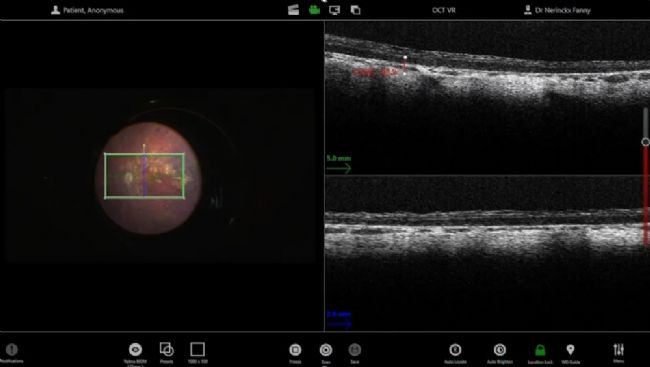

一旦水泡完全形成并注入所有液體,就會進行多次掃描并記錄以用于臨床試驗。對濾泡表面的掃描可以檢查黃斑中心凹的拉伸情況并確認沒有黃斑裂孔。還驗證了注射側,以確保視網膜切除術閉合。

圖 6:Nerinckx 博士在注射后利用腳踏板移動和控制 OCT 掃描,以檢查黃斑中心凹拉伸情況并確認沒有黃斑裂孔。

OCT 與 3D 平視系統(tǒng)的畫中畫集成有助于手術期間的注意力集中,尤其是在將插管固定在視網膜下方時。

圖 7:OCT 與 3D 平視系統(tǒng)的畫中畫集成。